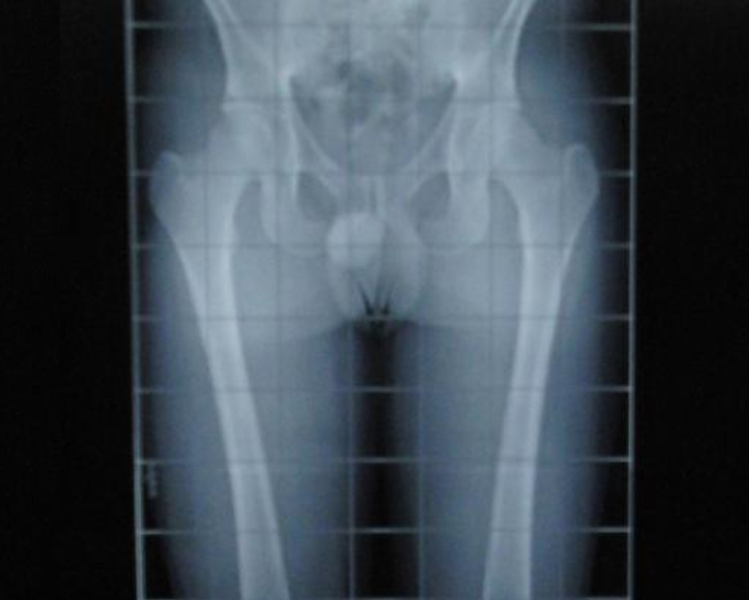

Dismetría de cadera: Qué es, cómo te afecta y tratamientos

La diferencia en longitud de miembros inferiores o disimetría, puede representar un problema funcional cuando rebasa los límites de la tolerancia. Es…